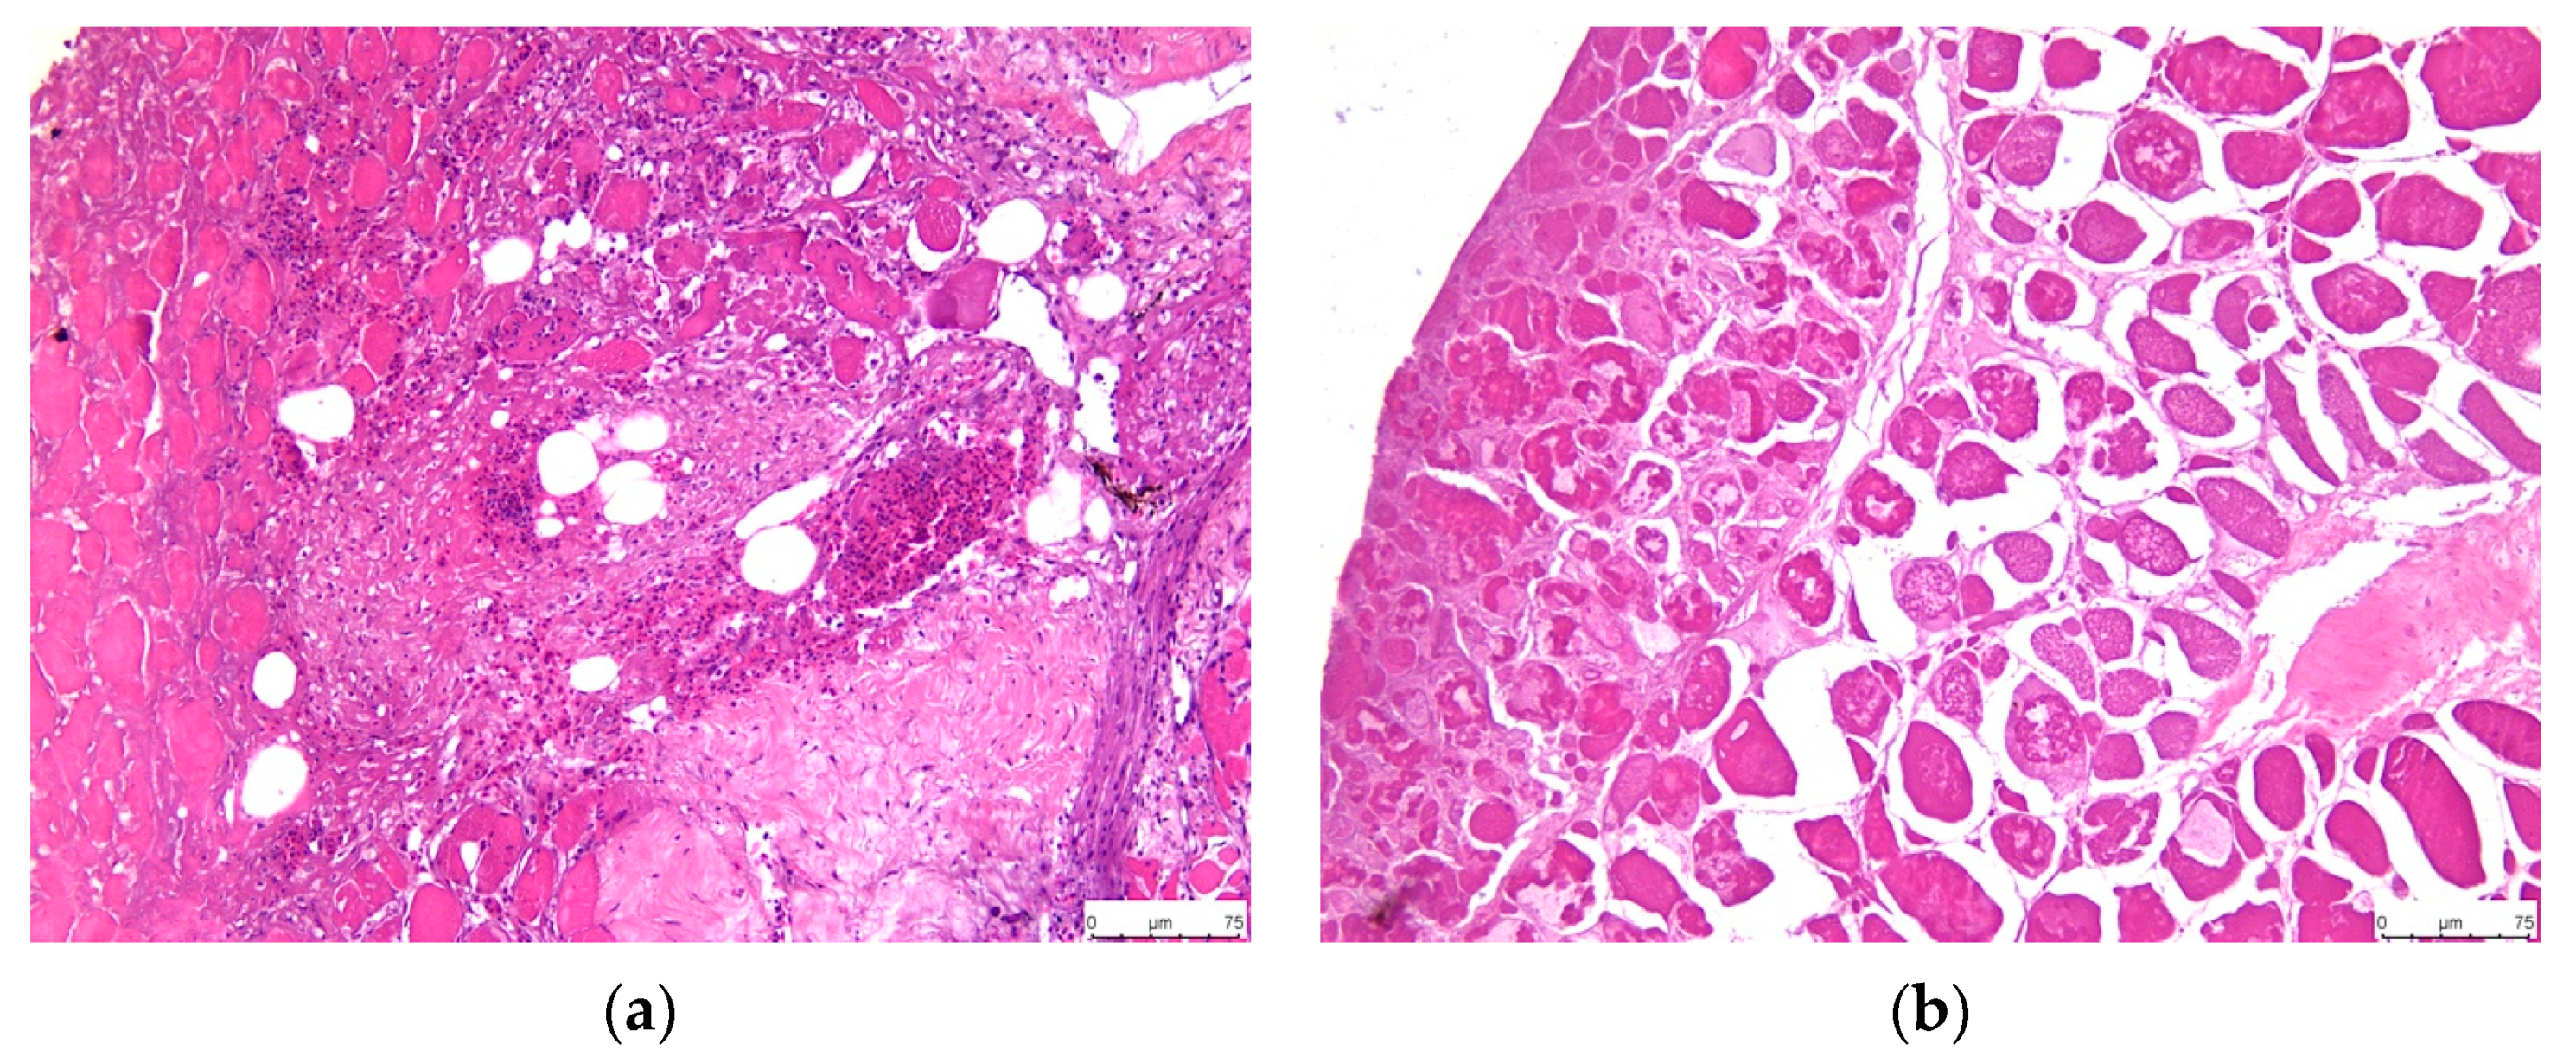

3.3.1. Scaled Skin and Skeletal Muscle

3.3.2. Spleen

3.3.3. Head Kidney

3.3.4. Abdominal Mesentery Fat